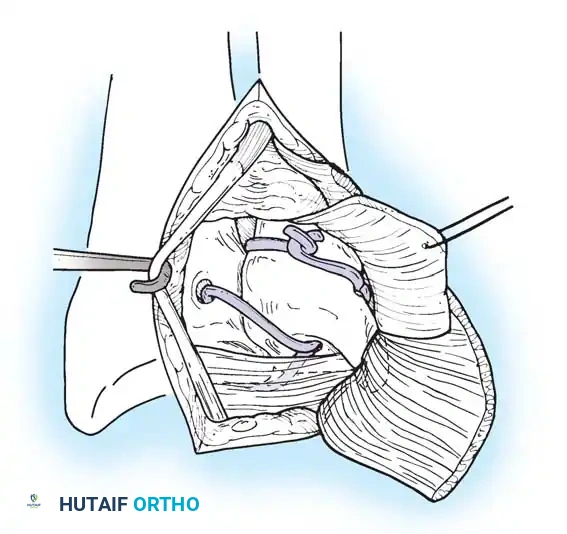

In cases of severe instability or concomitant ECU subsheath disruption, open capsular repair and ECU stabilization are required.

Open repair of the dorsal capsule and TFCC, ensuring robust closure and stabilization of the ulnar-sided structures.

Stabilization of the ECU tendon and subsheath, a critical step in addressing complex ulnar-sided wrist trauma.

If the DRUJ remains unstable after soft tissue repair, temporary transarticular K-wire fixation may be necessary to protect the repair during the initial healing phase.

Radiographic confirmation of temporary transarticular K-wire fixation stabilizing the DRUJ following complex TFCC repair.